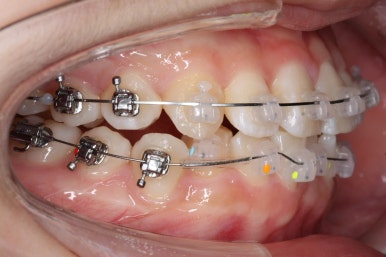

연산동교정치과에서 이번에 진행한 방법은 비발치교정이기 때문에 미니스크류를 잇몸뼈에 식립합니다.

위 사진에서 화살표 부분이 미니스크류인데요.

어금니쪽 잇몸에 아주 작은 나사가 보이실텐데요. 이것을 이용해서 전체 치열을 뒤로 당겨넣습니다. 물론 사랑니는 제거가 된 상태입니다.

아랫니도 어느 정도 많이 가지런해졌습니다.

윗니를 계속 당겨 넣습니다.

만족을 하실 때까지 계속계속 넣고 그리고 입 안에서는 허락하는 만큼 계속 당겨 넣습니다.

이제 아래쪽도 당겨 넣습니다.

원하는 만큼, 허락하는 만큼 계속 당겨 넣습니다. 연산동교정치과에서는 비발치 돌출입 교정을 위해 총 4개의 미니스크류를 식립했습니다.